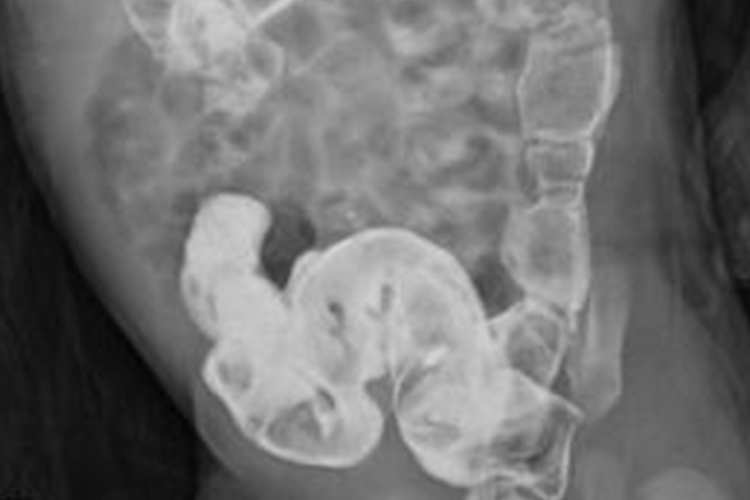

根据患者的典型症状如腹部膨隆如蛙状腹、肠形及肠型蠕动波等,配合肛门指检、X线、钡剂灌肠、直肠肛管测压等方法进行确诊。